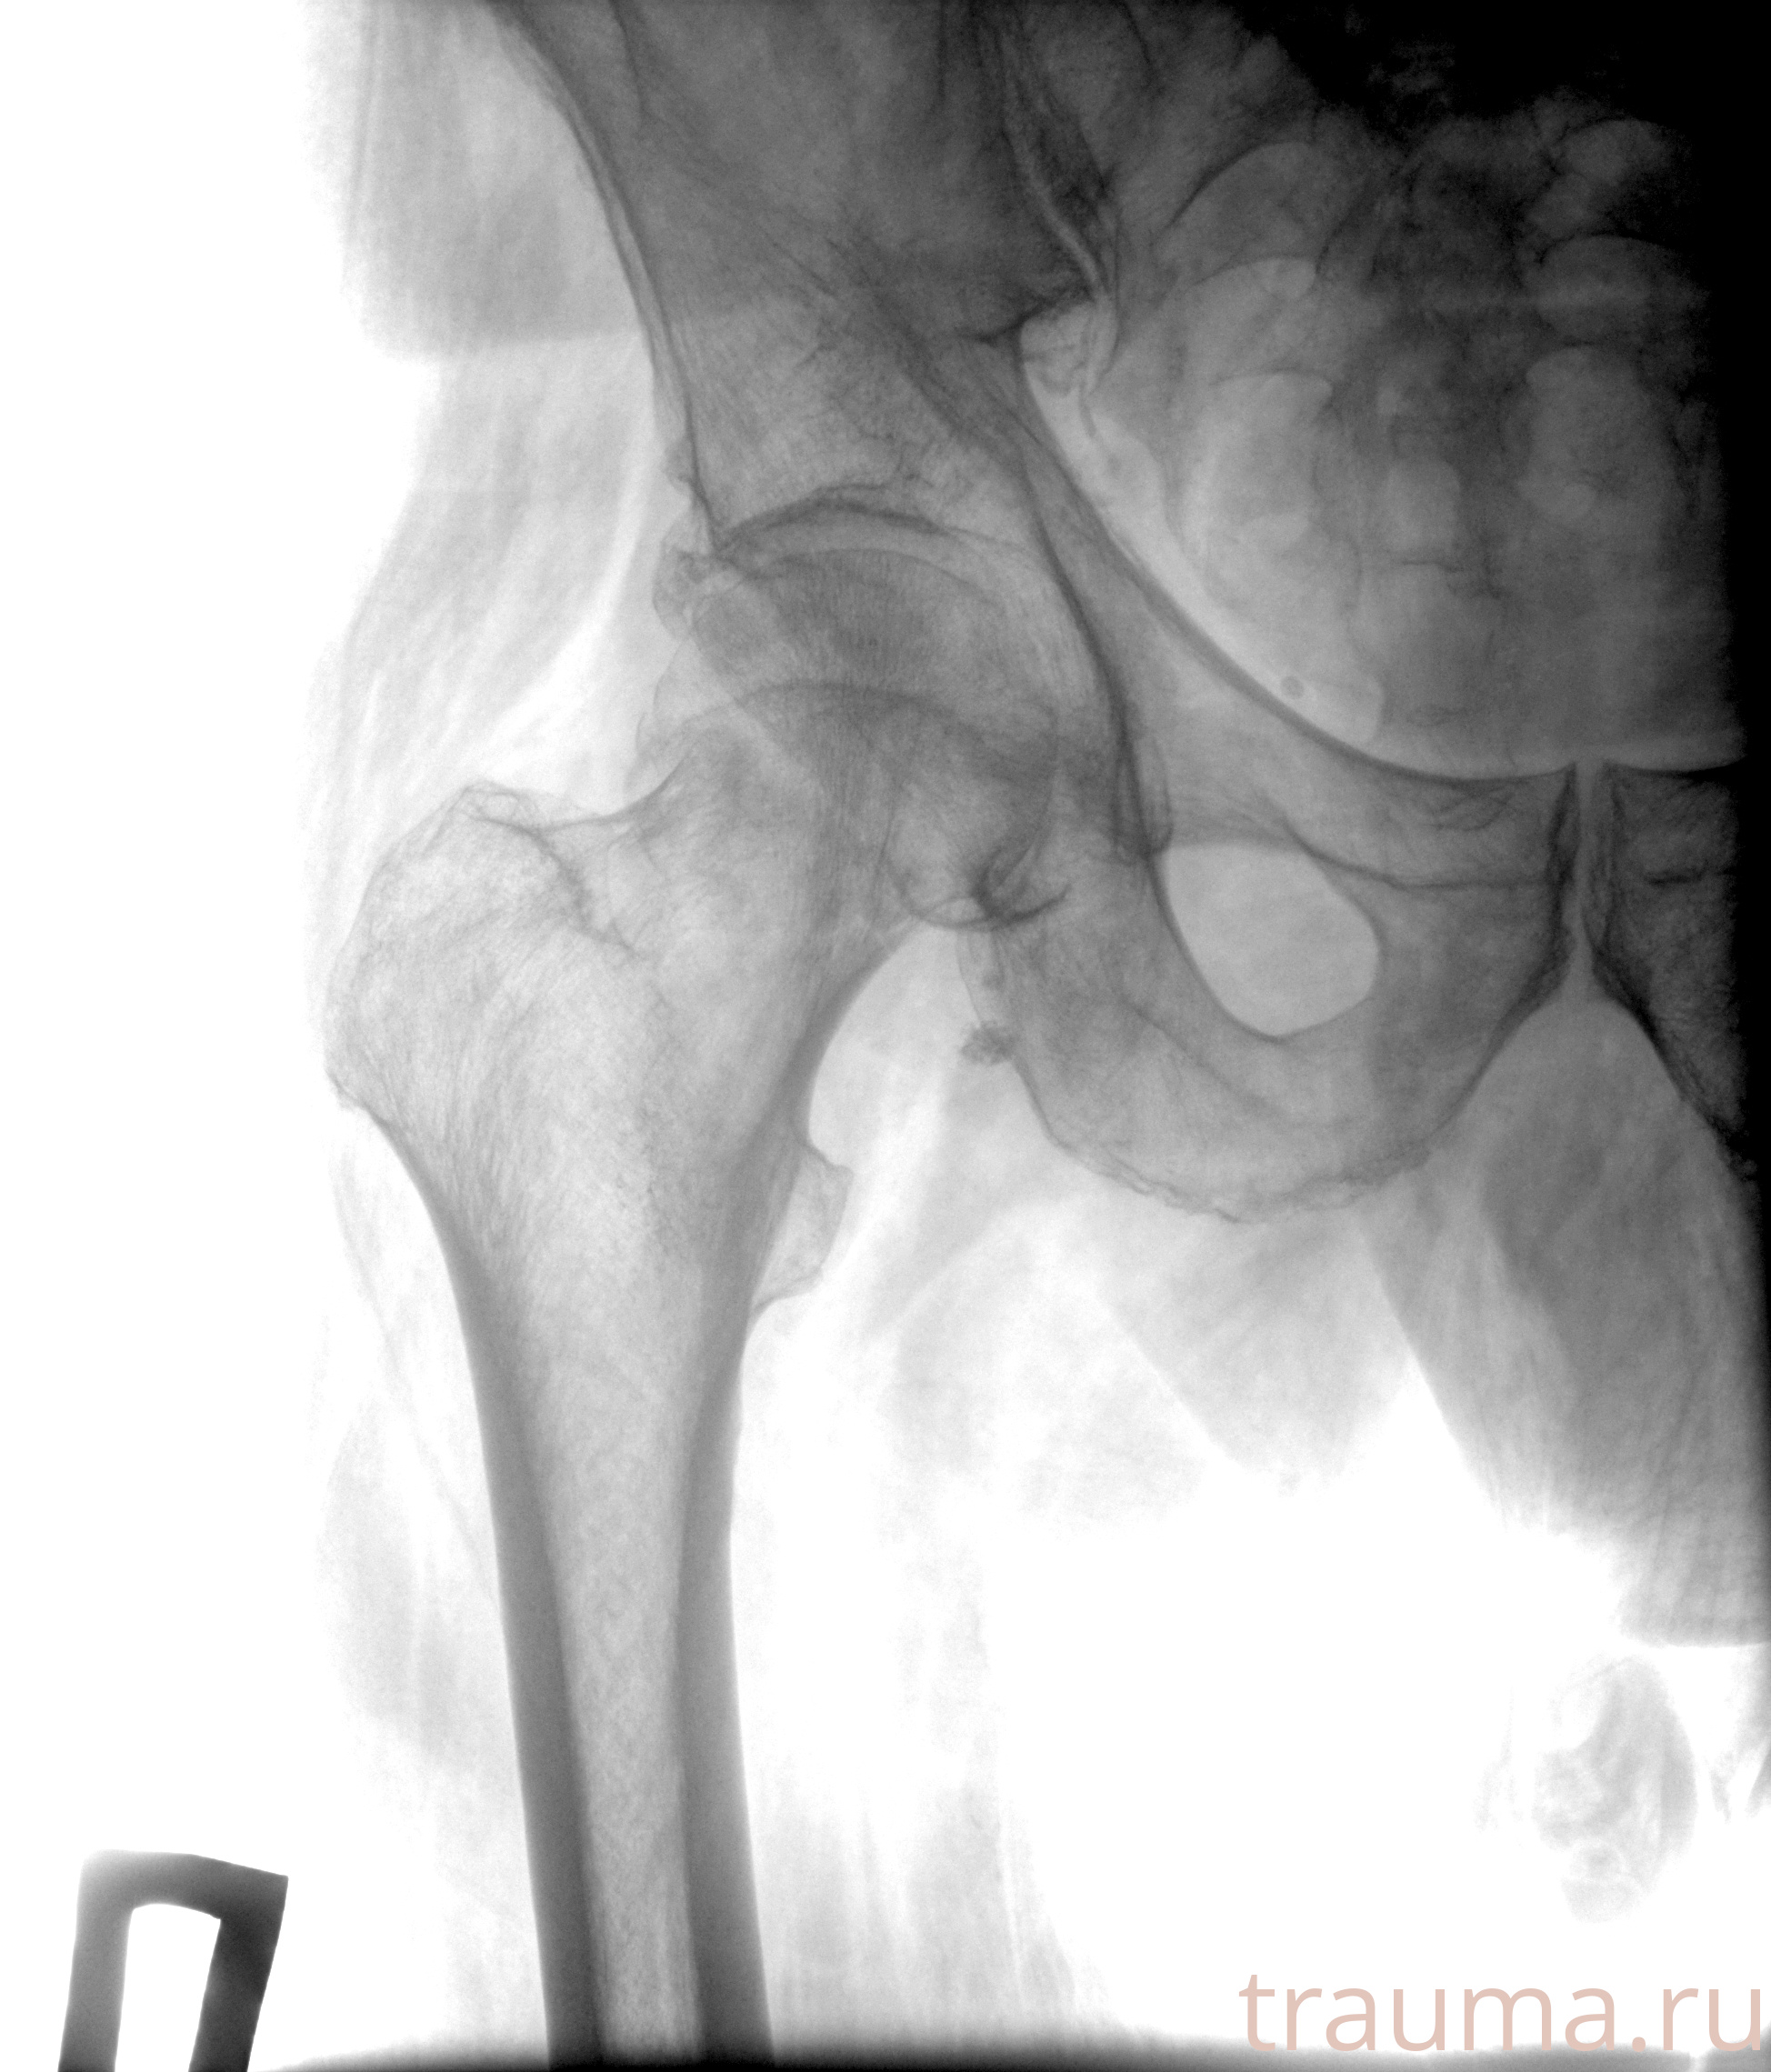

Рентгенограммы

Рентген на дому: по вашему адресу приезжает врач-рентгенолог, травматолог-ортопед с мобильным рентгеновским аппаратом, проводит диагностику травмы или заболевания, делает необходимые рентгенограммы, дает рекомендации по дальнейшему лечению. Получить качественные снимки в домашних условиях возможно благодаря уникальной методике, разработанной МосРентген Центром для института  Склифосовского